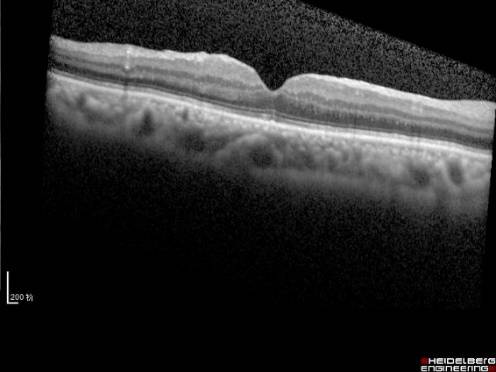

黄斑前膜

黄斑区的结构细微精细,其表面还有玻璃体后皮质和视网膜内界膜,有的时候,在后皮质和内界膜之间,会增殖产生一种特殊的病理性膜结构,叫黄斑前膜(见图10)。这层膜结构,与内界膜紧相连,同时也和玻璃体的后皮质紧密相连,当膜的增生,加上玻璃体的牵拉,使得黄斑被牵拉起来,于是产生视物的变形、视力下降。一旦产生了上述症状就需要及时通过玻璃体手术剥除增殖膜阻止视力的恶化,手术时间短,并发症少,大多数患者视力保持稳定,部分患者视力逐步提高。

图10. 黄斑前膜